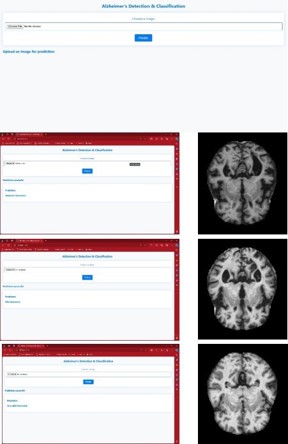

Deployment

The webpage is created using python. The figure 14 shows the web page that was created for the identification and classification of AD in which the input image can be chosen and a predict option is selected. The backend program will run and produce the result as the stages of the affected brain image.